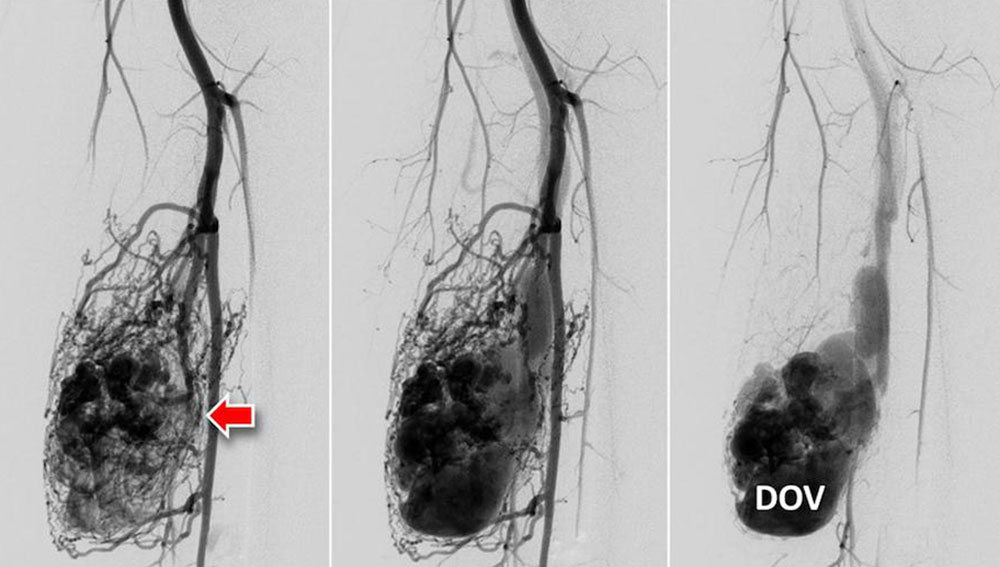

Fast-flow malformation (AVM and AVF): The exact anatomical morphology and the hemodynamics of a fast-flow vascular malformation can be very accurately analyzed with the use of DSA. The most important feature of a fast-flow vascular malformation is the immediate contrast filling of the draining veins via the nidus. Angiographically, fast-flow malformations can be categorized into four subtypes:

• In type I, there are up to 3 direct arteriovenous connections (AV fistulas) without an identifiable nidus

• In type II there is a dominant drainage vein, this can be aneurysmal.

• A fine fistulous, net-like nidus is called type IIIa.

• In type IIIb the net-like nidus is dilated.

In advanced disease, the incoming and outgoing vessels are also increasingly tortuous and dilated. In some cases, flow-related aneurysms are formed.